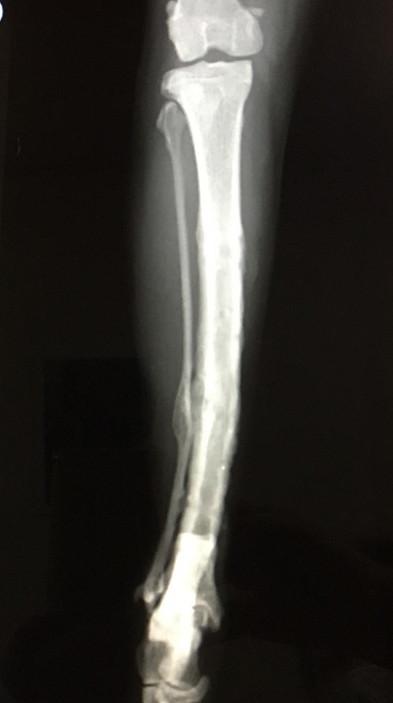

骨形成は順調

確かにまだボルトの穴はうっすら残ってるし、

今後トラブルの可能性も皆無じゃないから

12月に雪道で涙目になりながら行ってレントゲン撮って問題ないです言われて